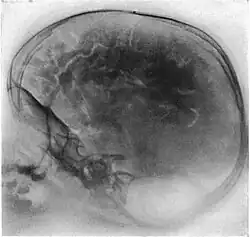

Die Pneumoenzephalographie oder Pneumoenzephalografie, auch Pneumoencephalografie, deutsch auch Luftenzephalographie (oder Luftenzephalografie), ist eine kontrastverstärkende Methode, oberflächliche Strukturen des Gehirns in konventionellen Röntgenaufnahmen als Pneumoenzephalogramm darzustellen. Sie wurde 1918/1919 vom amerikanischen Neurochirurgen Walter Edward Dandy eingeführt.[1][2][3] Diese Methodik galt damals als Meilenstein der Diagnostik, doch sie ist heute obsolet.

Bei einer Pneumoencephalografie wird der Liquor cerebrospinalis über einen lumbalen (siehe: Lumbalpunktion) oder subokzipitalen Zugang abgesogen und in gleichem Maße Luft eingeleitet. Durch Lagerung des Patienten kann nun erreicht werden, dass sich die Hirnwindungen gegen die Luft sehr deutlich abzeichnen. So konnten in vivo bei geschlossener Schädeldecke erstmals die Hirnwindungen radiografisch dargestellt werden und so bei neuralen Auffälligkeiten der Verdacht auf Tumore, Schwellungen oder Malformationen abgeklärt werden. Auch konnten so abgekapselte Hämatome (subdural wie epidural) sichtbar gemacht werden.